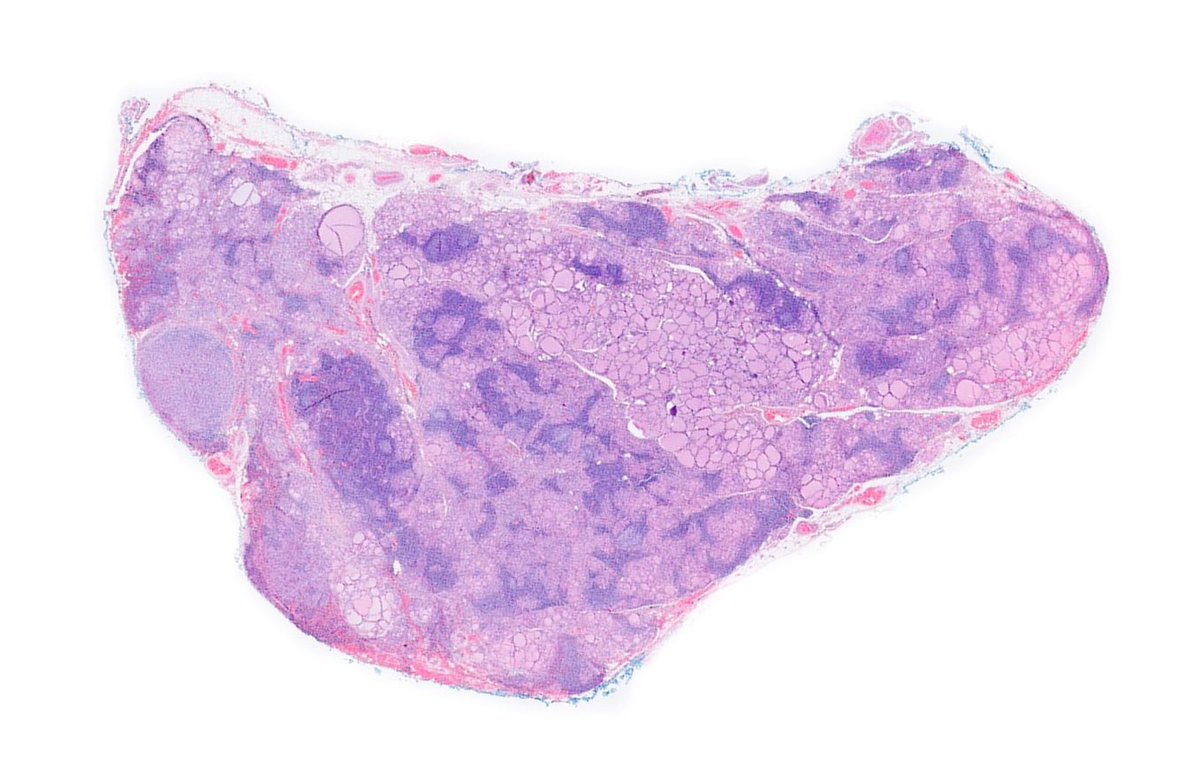

____ Follicular Variant Papillary Thyroid Carcinoma A) Non-invasive encapsulated B) Invasive encapsulated C) Invasive D) None of the above 🔬dpa-dapa.com/public/display… #EndoPath #ENTPath #PathTwitter #PathResidents

A) Non-invasive encapsulated

B) Invasive encapsulated

C) Invasive

D) None of the above